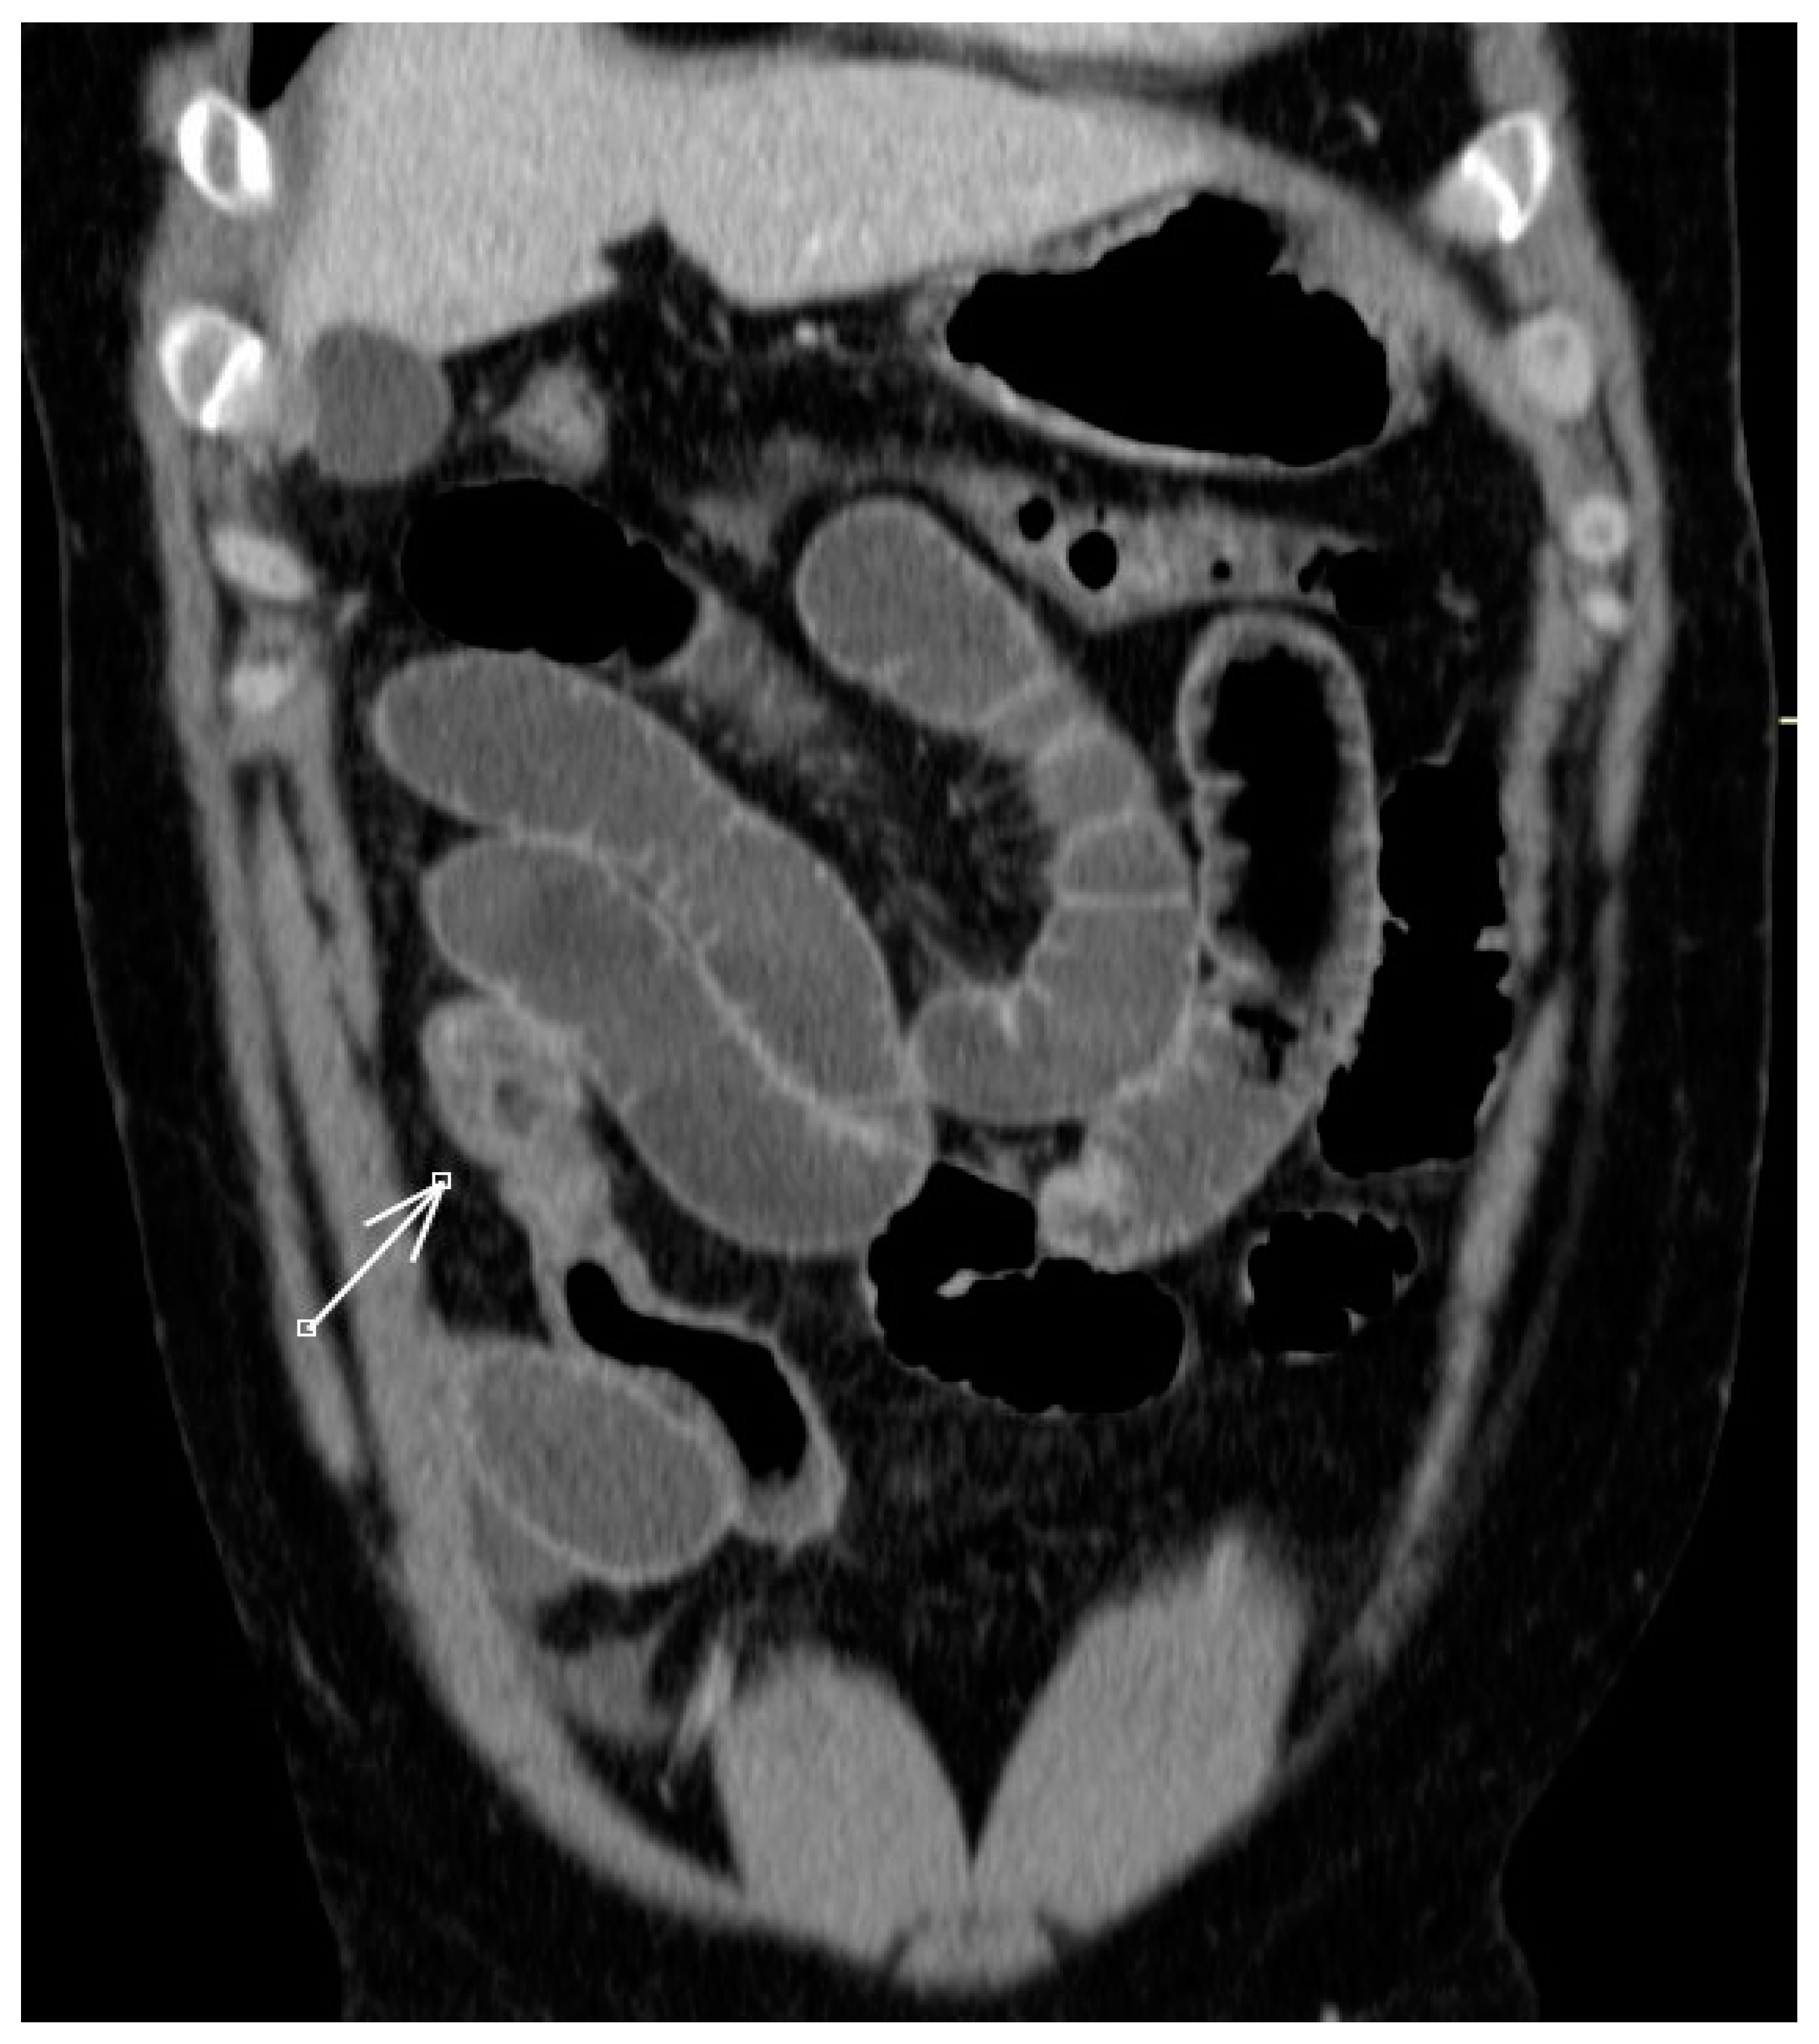

2. Case Description

- Shibata, E.; Ueda, T.; Akaike, G.; Saida, Y. CT Findings of Gastric and Intestinal Anisakiasis. Abdom. Imaging 2014, 39, 257–261. [Google Scholar] [CrossRef]

- Fornell Pérez, R.; Urizar Gorosarri, M.; Pérez Bea, M. Anisakiasis: Imaging findings. Radiologia 2022, 64, 245–255. [Google Scholar] [CrossRef] [PubMed]